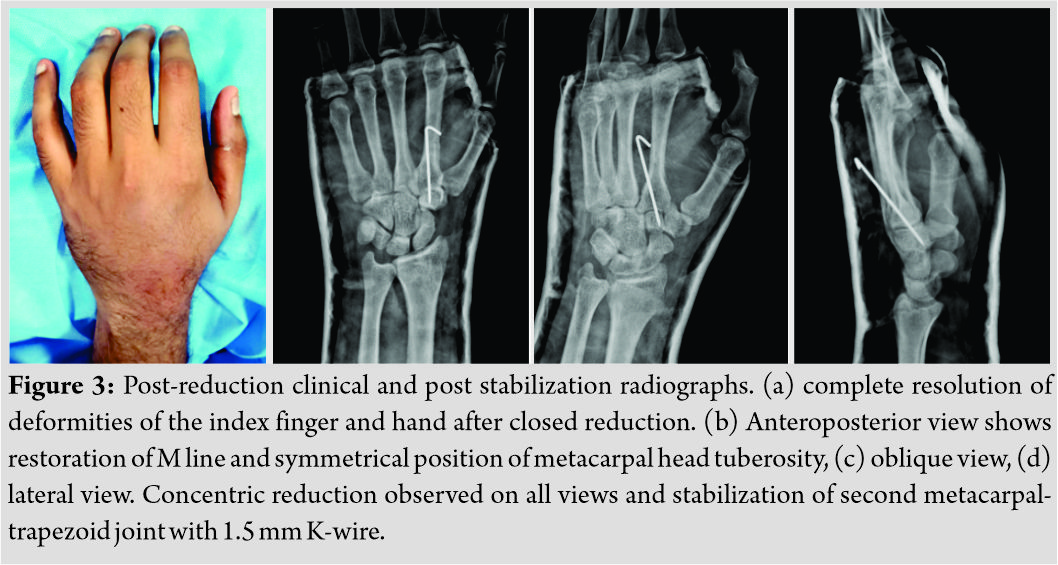

The computed tomography (CT) scan of the left wrist revealed the same, and no associated carpal injuries were observed (Fig. 2a-c). Under general anesthesia, a closed manipulation was attempted in the form of exaggerating the deformity and maneuvering a gentle distally directed force over the dislocated second metacarpal base which reduced with clunk and resolution of the deformities (Fig. 3a). The concentric reduction was attained and the articulation stabilized with a 1.5 mm Kirschner wire (K-wire) passed percutaneously under fluoroscopy guidance (Fig. 3b-d).

Under general anesthesia, a closed manipulation was attempted in the form of exaggerating the deformity and maneuvering a gentle distally directed force over the dislocated second metacarpal base which reduced with clunk and resolution of the deformities (Fig. 3a). The concentric reduction was attained and the articulation stabilized with a 1.5 mm Kirschner wire (K-wire) passed percutaneously under fluoroscopy guidance (Fig. 3b-d).  A below elbow cast with the wrist in 30° dorsiflexion was given for 3 weeks further which the K-wires were removed and rehabilitation instituted. The patient regained full range of hand functions, similar to pre-trauma status and returned to routine activities. Over the 13 months period of follow-up, no recurrent episodes or radiological evidence of arthritis were observed.